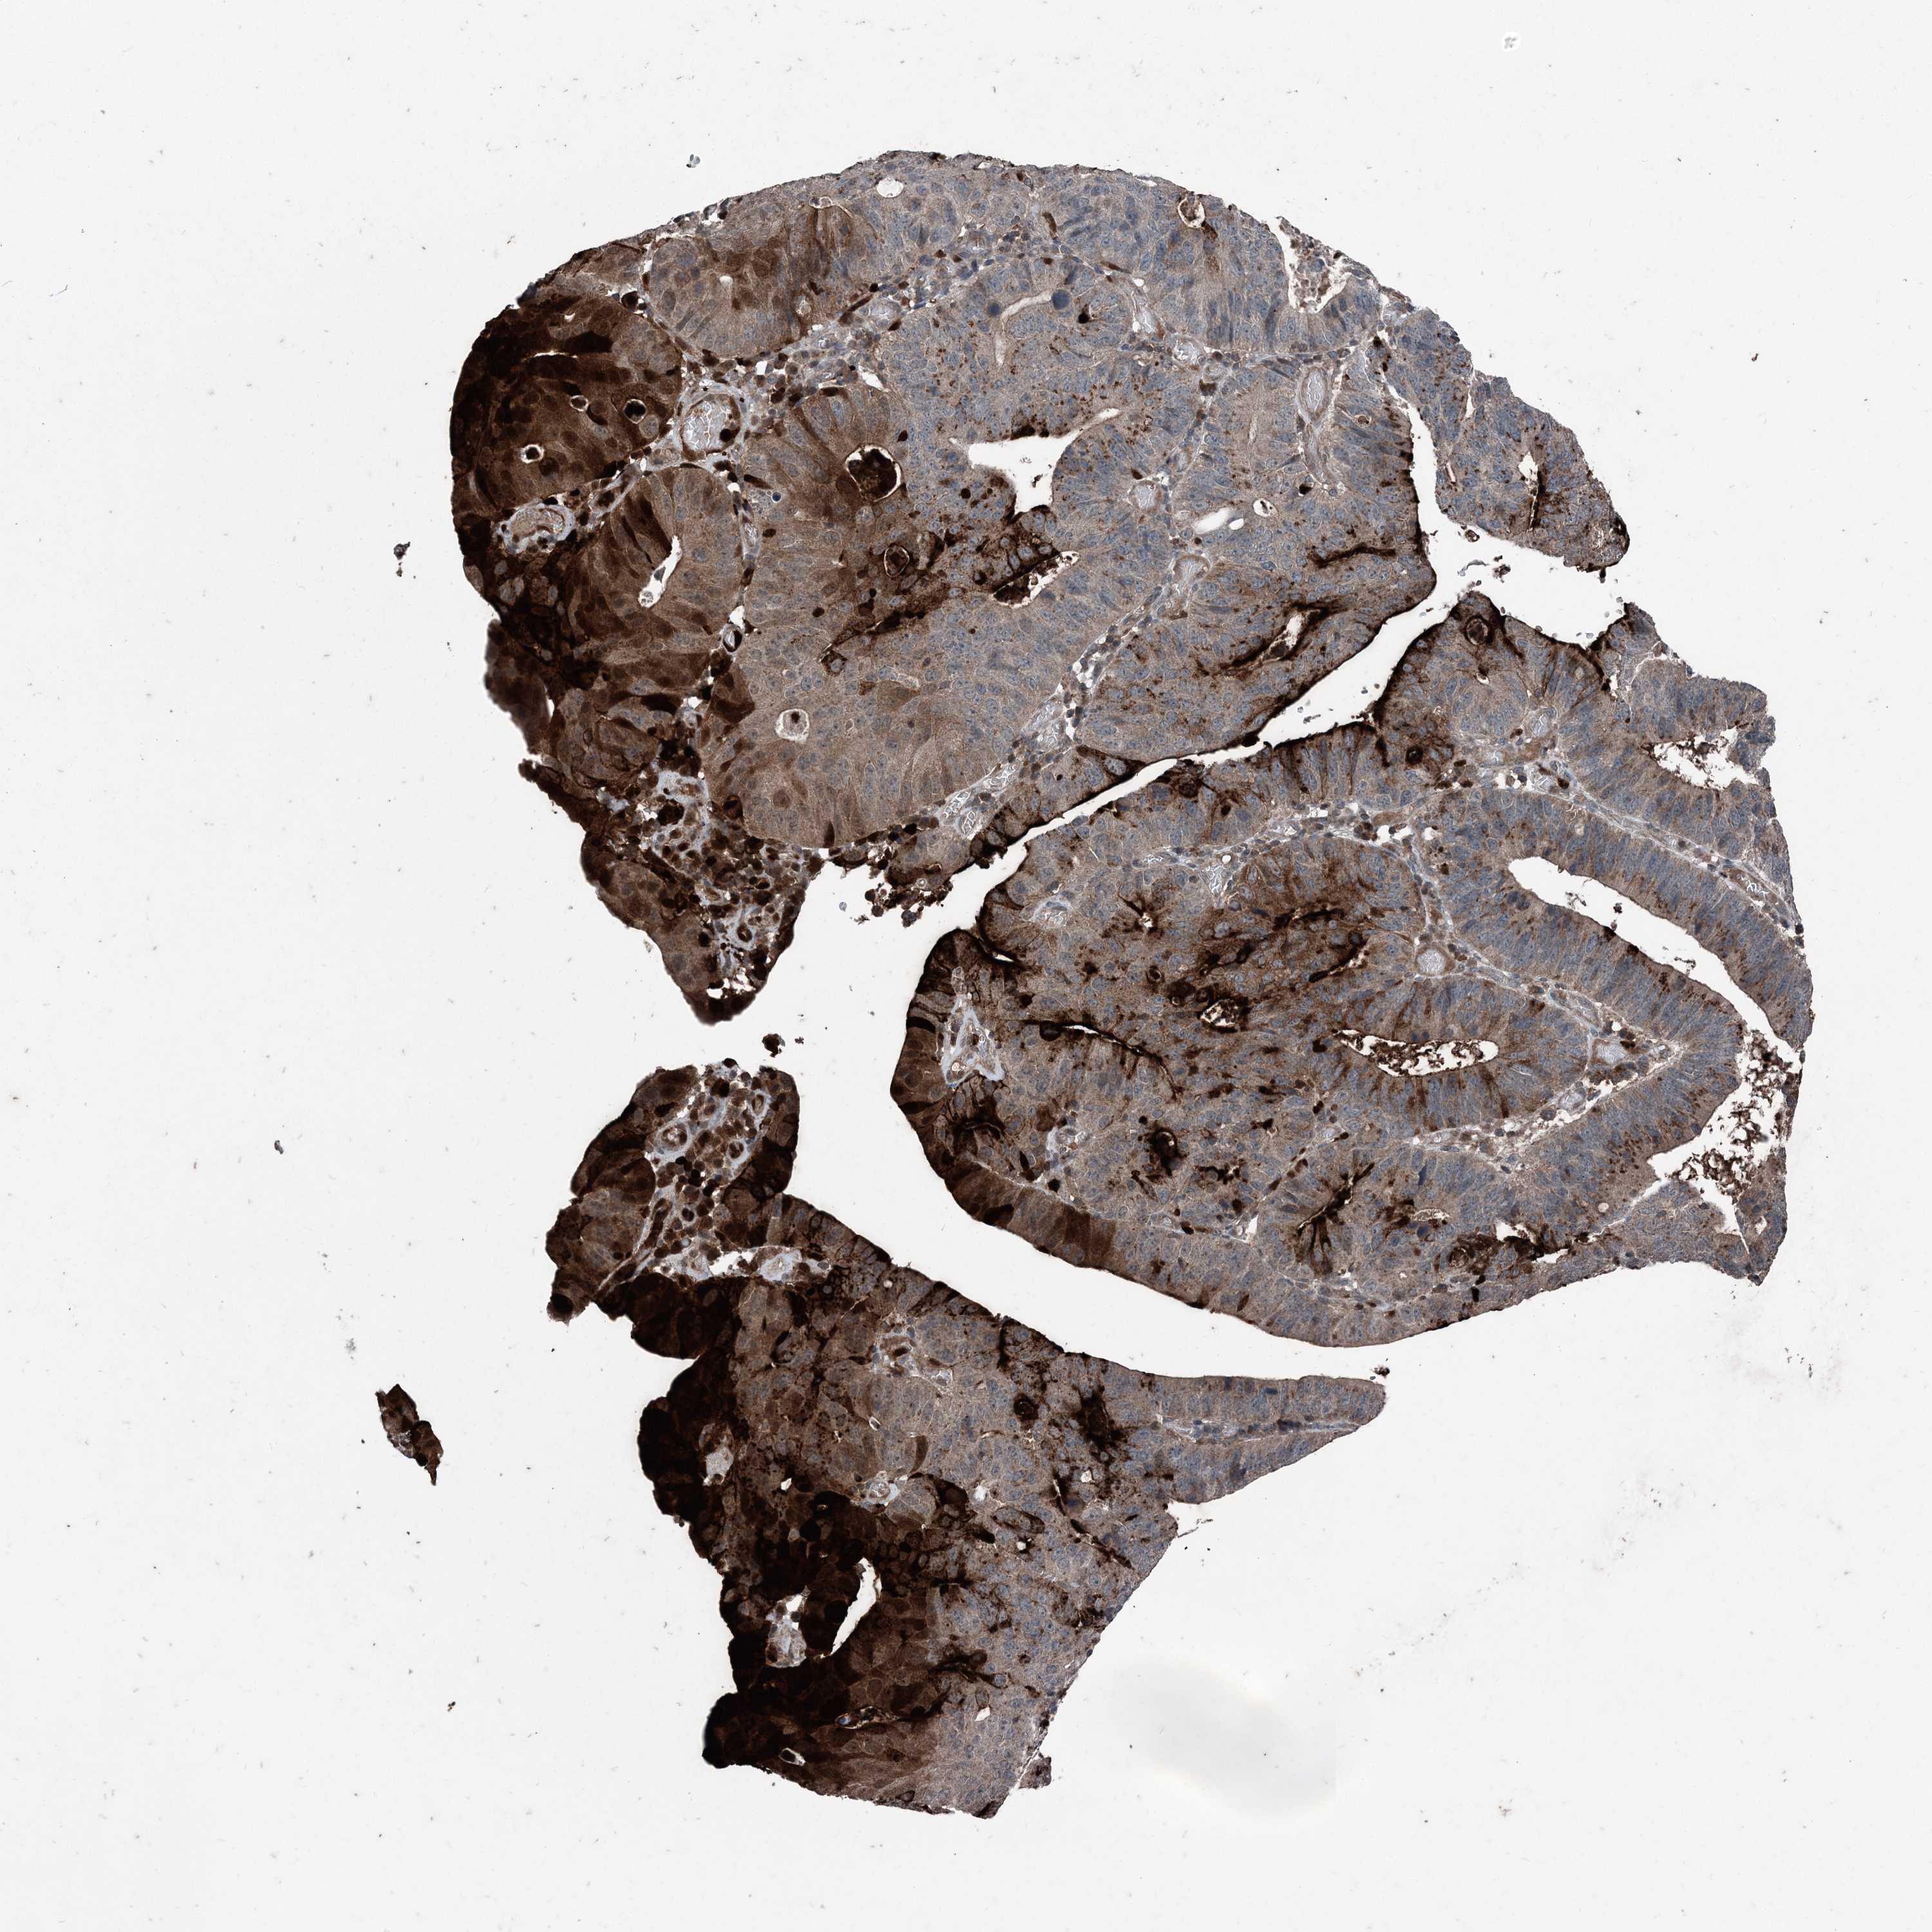

STOMACH CANCER - Protein expressioni

A mouse-over function shows sample information and annotation data. Click on an image to view it in a full screen mode. Samples can be filtered based on level of antibody staining by selecting one or several of the following categories: high, medium, low and not detected. The assay and annotation is described here.

Note that samples used for immunohistochemistry by the Human Protein Atlas do not correspond to samples in the TCGA dataset.

Antibody stainingi

Antibody staining in the annotated cell types in the current human tissue is reported as not detected, low, medium, or high, based on conventional immunohistochemistry profiling in selected tissues. This score is based on the combination of the staining intensity and fraction of stained cells.

Each image is clickable and will lead to virtual microscopy that enables deeper exploration of all samples and also displays staining intensity scores, fraction scores and subcellular localization as well as patient and tissue information for each sample.

Antibody HPA053761

Antibody CAB033687

Antibody CAB037077

Staining

High

Medium

Low

Not detected

Intensity

Strong

Moderate

Weak

Negative

Quantity

>75%

75%-25%

<25%

None

Location

Nuclear

Cytoplasmic/membranous

Cytoplasmic/membranous,nuclear

Adenocarcinoma, NOS